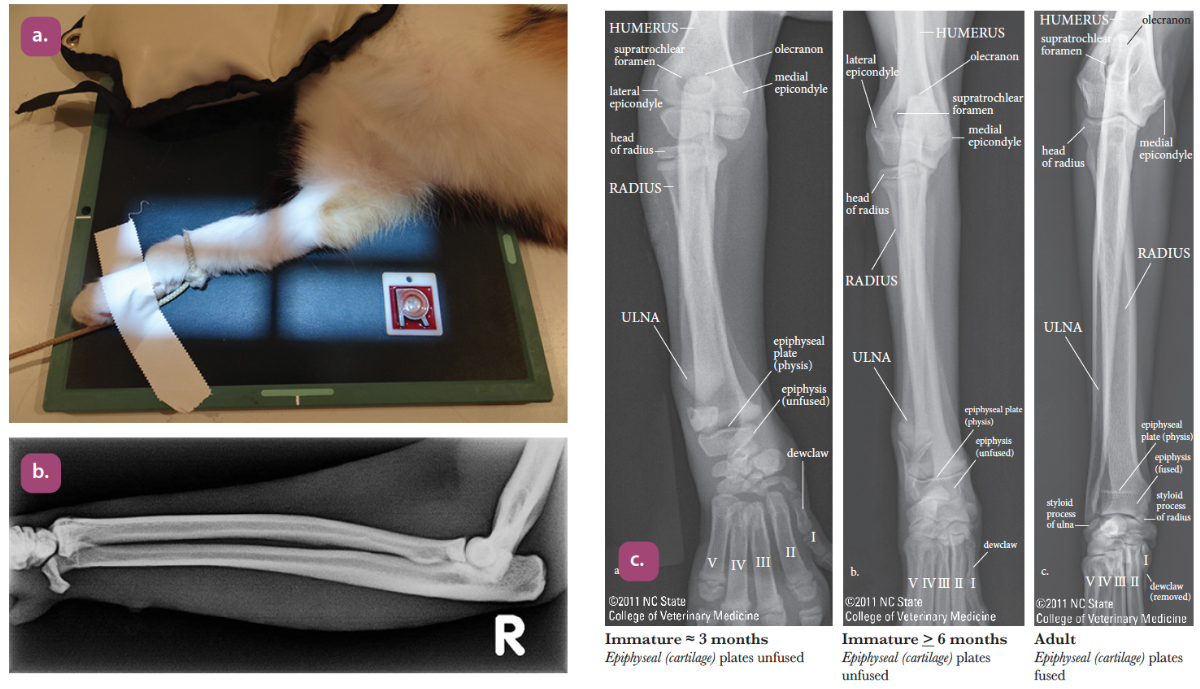

mediolateral projection of the elbow

craniocaudal projection of the elbow

flexed mediolateral projection of the elbow

mediolateral projection of the radius and ulna

craniocaudal projection of the radius and ulna